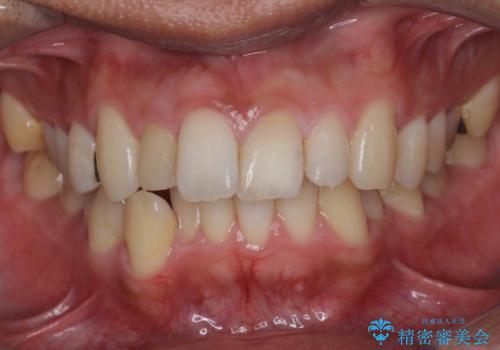

- 他院で右上の前歯の状態が悪いことを指摘されて来院。

昔ぶつけてしまった既往がありました。

歯の根の部分が内部で吸収し、周りの骨も吸収してしまっていました。

このまま放置すると、骨の吸収も進行し、いずれ近い将来歯が折れてしまう可能性もありました。また、隣の歯にも骨の吸収による影響が始まっており、持たせるだけ持たせたとしても次のステップの時には状況が悪化してしまうことが予想されました。

以上を説明したところ、早めに抜歯を行いブリッジにしていくことを希望されたため治療開始しました。

右上2番の周りの歯槽骨がかなり吸収が進んでいた影響で、抜歯後そこが大きくへこむことが予想されました。

抜歯後即時にバイオスを詰めることで抜歯後の骨の吸収をなるべく抑える治療(ソケットプリザベーション)を行いました。

歯槽骨が吸収してしまった右上1(隣の歯)との境界については右上1番遠心の歯周ポケットが深いことについては解決できない為、いずれまたダミーの歯の部分に関しては歯肉が下がってしまうことについては説明済みです。

ただ、年齢も鑑みて、直ちに右上12抜歯ではなく、まずは2番のみの抜歯でブリッジにする処置を行いました。